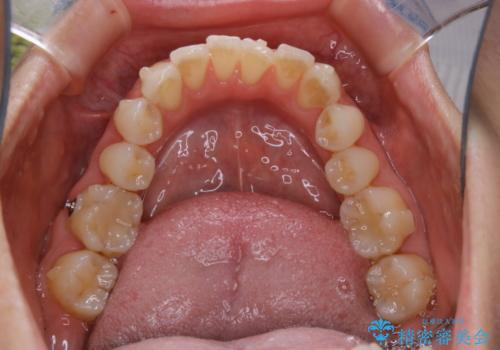

- インビザライン矯正治療中にステインが気になるとのことで来院されました。全体的にステインが付着していたため自費クリーニングPMTC(60分コース)を行いました。

インビザライン矯正治療中は、ご自身の歯にアタッチメントという突起物(効率的に歯の移動を行うため)をつけます。そのため、通常時よりもステインが付きやすい状態になることがあります。

インビザラインは透明なマウスピースなので、ご自身の歯にステインなどが付着していると、見た目に影響してしまうことがあります。

矯正治療中の虫歯・歯周病・口臭予防としても、定期的にPMTCを行うことが大切です。